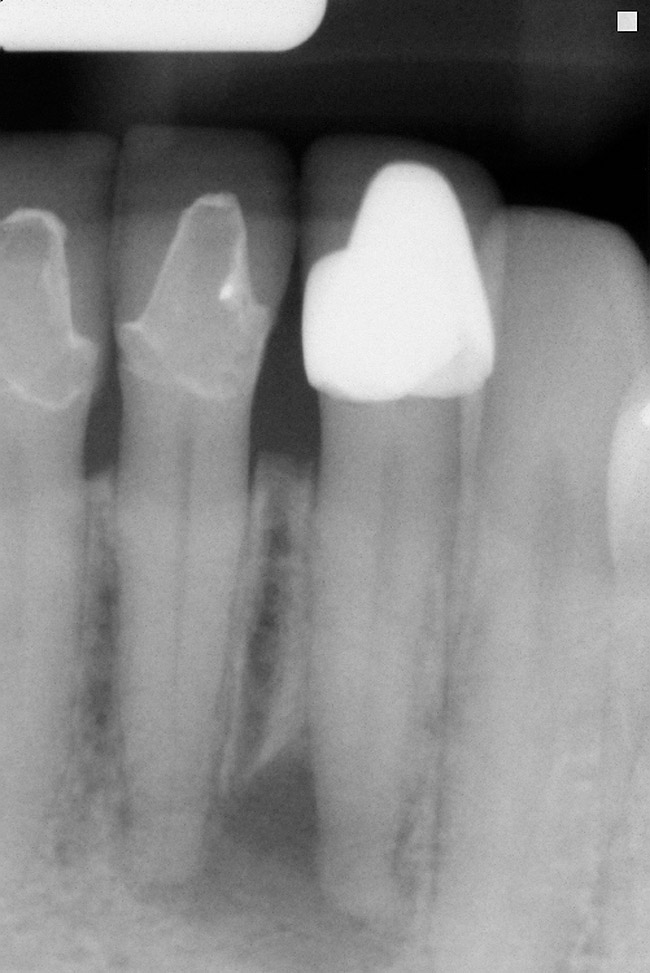

A tooth that is deemed structurally restorable and periodontally sound that requires endodontic therapy has an overall success rate of 90%. There are certain conditions that lower the success rate of which the clinician needs to be aware. According to the Toronto Study,34 a longitudinal study, a vital tooth requiring initial therapy will have a success rate of 93%. A non-vital tooth with a periapical radiolucency < 5 mm will have a 89% success rate.34 A non-vital tooth with periapical radiolucency > 5 mm will have a 74% success rate.34 Clearly, a tooth with periapical radiolucency > 5 mm significantly decreases the success rate of endodontic therapy (Figure 12).

Figure 12  ENDODONTIC AND ESTHETIC PARAMETERS A tooth with a periapical radiolucency > 5 mm significantly decreases the success rate of endodontic therapy.

Figure 12